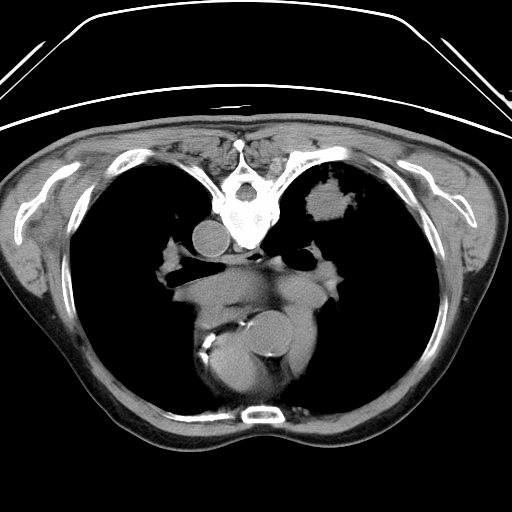

CT引导下治疗操作中

通过局部消毒,局部麻醉后在CT引导下将直径2毫米射频针准确刺入肿瘤中心,10分钟后结束治疗,术中患者无明显不适,术后患者自行走回病房,3天后出院。